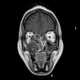

Paranasal sinusitis

Sinusitis, also known as rhinosinusitis, is inflammation of the mucous membranes that line the sinuses resulting in symptoms that may include thick nasal mucus, a plugged nose, and facial pain. Other signs and symptoms may include fever, headaches, a poor sense of smell, sore throat, and a cough. [Source: Wikipedia ]